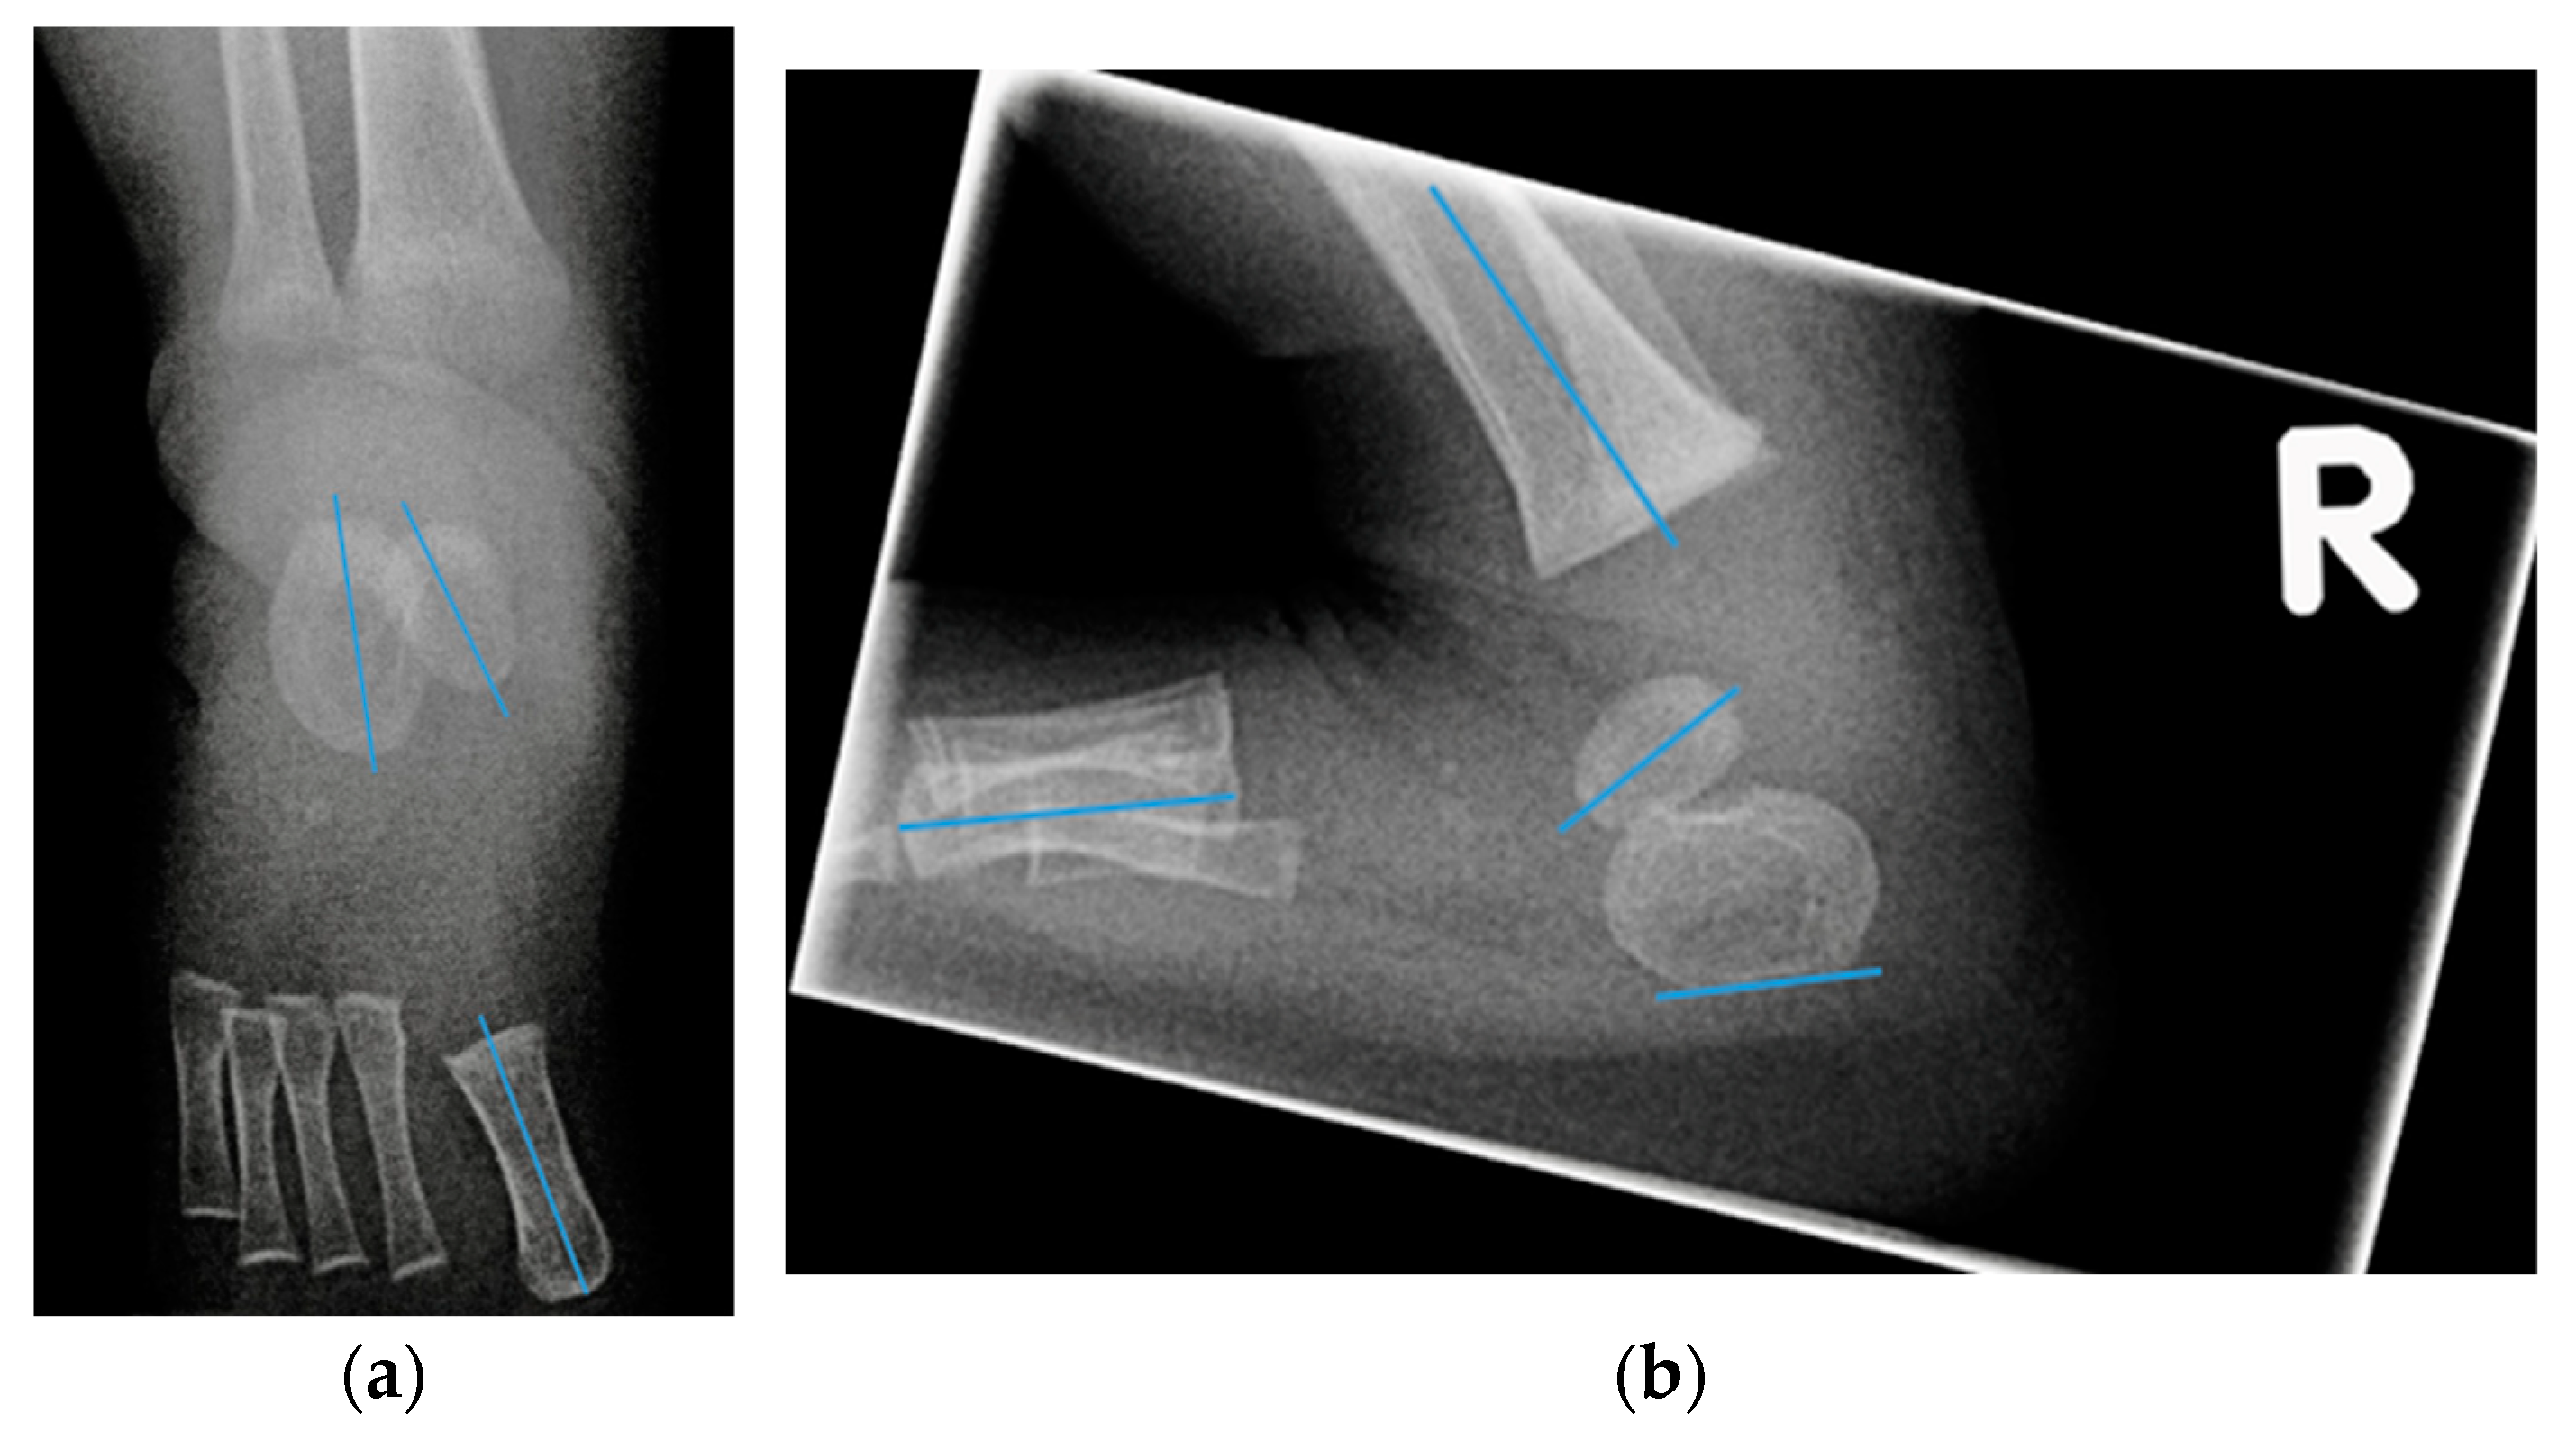

- Talocalcaneal angle (AP talocalcaneal): the angle between the long axes of the talus and calcaneus. This measurement describes the eversion of the calcaneus under the talus. A small value indicates hindfoot varus [9].

- Talo first metatarsal angle (AP talo 1st MT): the angle between the long axis of the talus and 1st metatarsal. This measurement describes forefoot abduction or adduction [9].

- Lateral tibial calcaneal angle (lat tibiocalcaneal): the angle between longitudinal axis of the tibia and the plantar aspect of the calcaneus. This measurement describes equinus deformity.

- Lateral talo first metatarsal angle (lat talo 1st MT): the angle between the long axis of the talus and the first metatarsal. This measurement describes the presence of cavus deformity.

- Lateral calcaneal 1st metatarsal angle (lat calcaneal 1st MT): the angle between the plantar aspect of the calcaneus and the long axis of the first metatarsal. This measurement also describes the presence of cavus deformity.

- Foot dorsiflexion between the tibia and a radiolucent wooden board in maximum dorsiflexion (lat foot dorsiflexion). This measurement describes equinus.